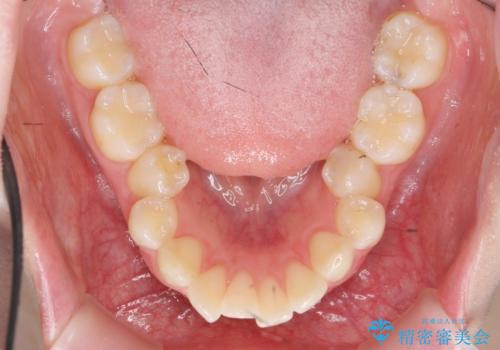

- 口が閉じづらく、突出し歯が出っ歯に見えてしまうことの改善を求めて来院されました。

通常このような場合、抜歯してのワイヤー矯正治療も選択肢に入りますが、患者様の強い希望により抜歯を行わずマウスピースによる治療を選択しました。

カリエール・マイクロインプラントを用い、時間はかかりましたが大きく歯の後方移動が達成され、前歯の見た目が大きく改善されました。